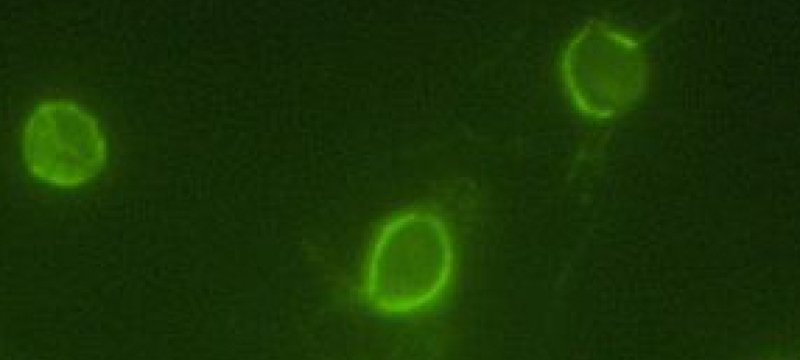

Very big news out of cellular biology and the Striepen lab in the fight against a parasite known as a major cause of suffering throughout the developing world: Researchers at the University of Georgia have developed new tools to study and genetically manipulate cryptosporidium, a microscopic…